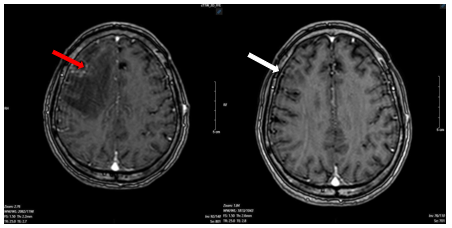

Bệnh nhân được chỉ định các xét nghiệm phương tiện cận lâm sàng khác. Trên phim chụp cắt lớp vi tính lồng ngực - ổ bụng của bệnh nhân phát hiện khối u phổi có kích thước ~ 32 x 30 mm ở thùy trên phổi trái và hình ảnh khối u gan ngấm thuốc viền - theo dõi thứ phát.

Hình 2.

Hình ảnh khối u phổi phải trên phim chụp Cắt lớp vi tính ngày 19 tháng 03 năm 2025 (mũi tên).